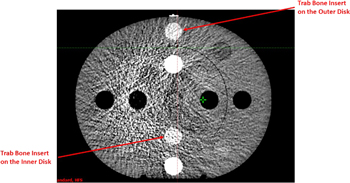

For 100 kV, not only was the HU deviation between the reference scan and other scans substantial, but the standard deviation of most scatter conditions was out of tolerance, rendering them unsuitable for dose calculations. This is because the 100 kV Head protocol is designed specifically for the H&N configuration, the typical width and length of which is approximately 15 cm and 18 cm, respectively. Therefore, when only the inner disk of the CIRS CTED phantom was scanned, both the reproducibility and the SNR of the scan were acceptable. In contrast, for the other scans where the geometry of the scanned material was larger, both the HU difference and the standard deviation were out of tolerance (i.e., >50 HU in the adipose—liver range or >100 HU in other materials). An example of Scan 4 acquired with the 100 kV Head protocol on HAL1 is shown in figure 5, which illustrates both the HU deviation between the inner and the outer disks as well as the increased noise.

Figure 5. CBCT image of the CIRS CTED phantom acquired with the 100 kV Head protocol. Obvious noise and artefacts were observed. The two trabecular bone (Trab Bone) inserts, which had the same density, are highlighted.

Standard image High-resolution imageHU response results for the 125 kV and 140 kV protocols were similar across the scan variants. Table 5 shows that the standard deviations of both tube voltages were within the tolerance across the two linacs, indicating that the SNRs of both protocols were acceptable. This can also be seen from figure 6, which, compared to figure 5, shows significantly higher SNR under the same scatter condition.

Figure 6. CBCT image of the CIRS CTED phantom acquired with the 125 kV Pelvis protocol.